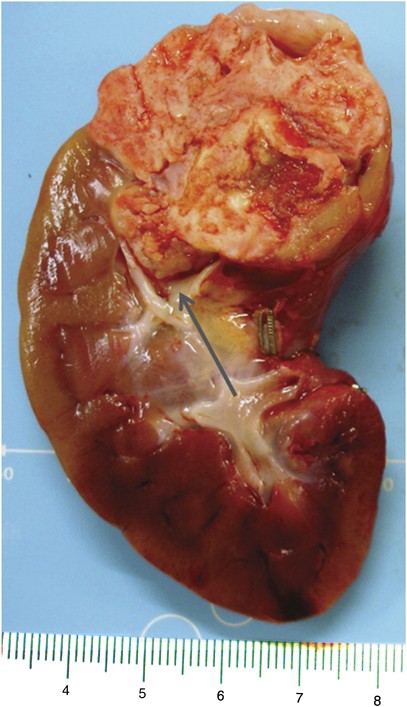

The index case, case A, was that of a 1-year-old male who presented with hematuria and was found to have a 3.5-cm, in maximum diameter, stony hard mass in the upper pole of the right kidney, bulging within the pelvi–caliceal system (Figure 1). The patient underwent a nephrectomy. Histologically, the tumor was heterogeneous, composed mainly of osteoid trabeculae and mature bone lined by osteoblasts and some osteoclasts with no atypical features. Wedged between the osteoid and ossified trabeculae were islands of eosinophilic epithelioid cells. Other spaces contained loose to mildly compact spindle cells (Figure 2). Necrosis and mitotic figures were not seen. The tumor was well demarcated from the surrounding renal tissue that showed compression with tubular atrophy, but no encapsulation. There was no evidence of intra or perilobar nephroblastomatosis. Immunohistochemistry was non-contributory and, in particular, did not detect a nuclear WT1 antigen.